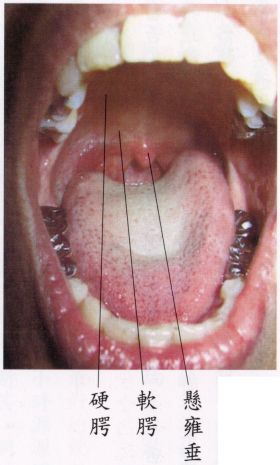

当舌尖顶‘上门牙后约一、二公分处’,‘舌面’和‘软|’保持距离(部位见下面图示),而放松时,立即会觉得‘悬雍垂’(俗称喉咙钟)后方之咽喉,通风清凉,呼吸道有如‘拓宽’而出入息通畅。越放松、越能感受呼吸时顶上清凉,不昏沉。

┌前―硬|:与骨相贴之硬部。上|

上|│

└后―软|:悬空之软部。

(中有‘悬雍垂’)